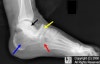

X-ray : Chopart injury